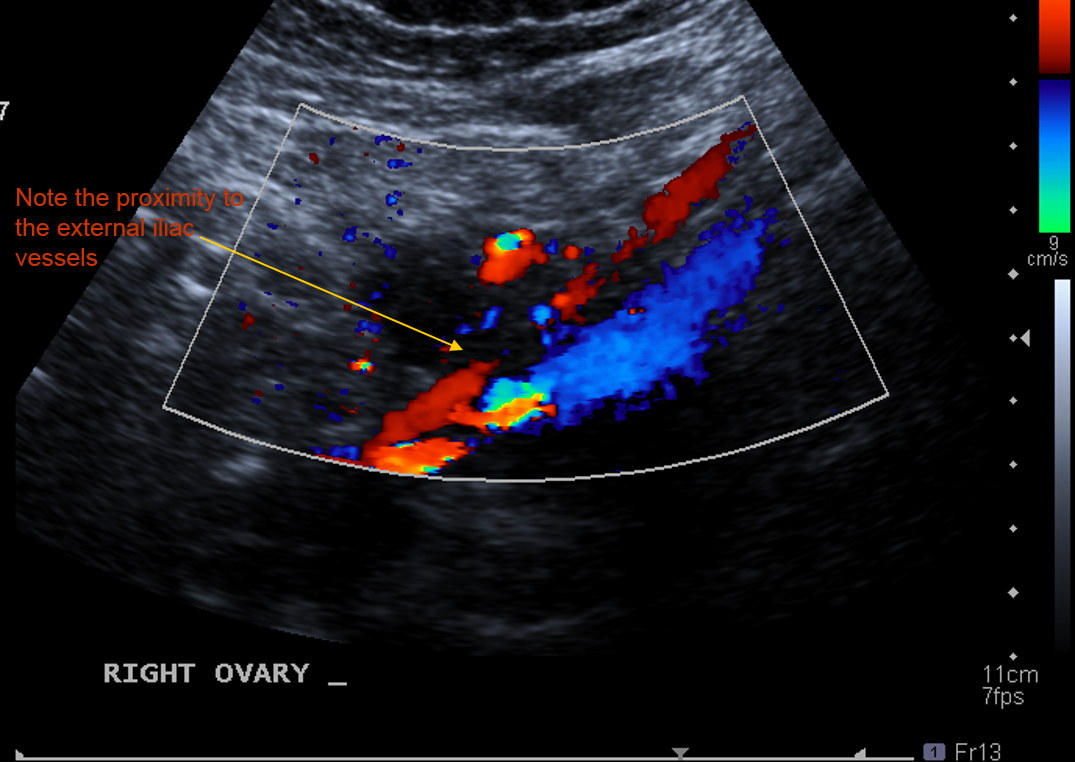

What vascular strcture can the ovaries be shown to be closely related to ?

The R and L external iliac vessels